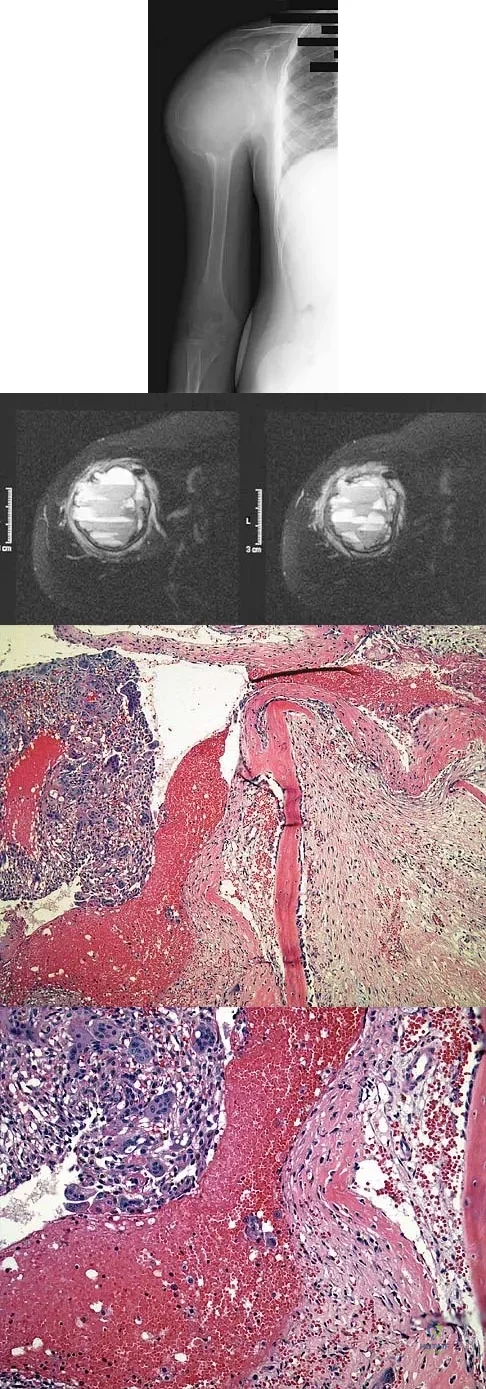

Question 88

A 15-year-old boy has had pain in the right shoulder for the past 3 months. He denies any history of trauma and has no constitutional symptoms. Examination reveals a large firm mass in the proximal arm. A radiograph and MRI scan are shown in Figures 27a and 27b. Biopsy specimens are shown in Figures 27c and 27d. Management should consist of

Explanation